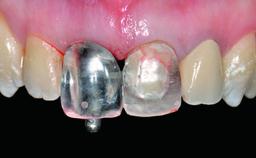

Replacement of an Ankylosed Central Incisor with a Gingival Recession: Tooth Extraction with Socket Grafting and Late Implant Placement with Simultaneous Contour Augmentation

Abutment Type CAD/CAM

Prosthesis Type FDP

Retention Screw-retained Screw-retained